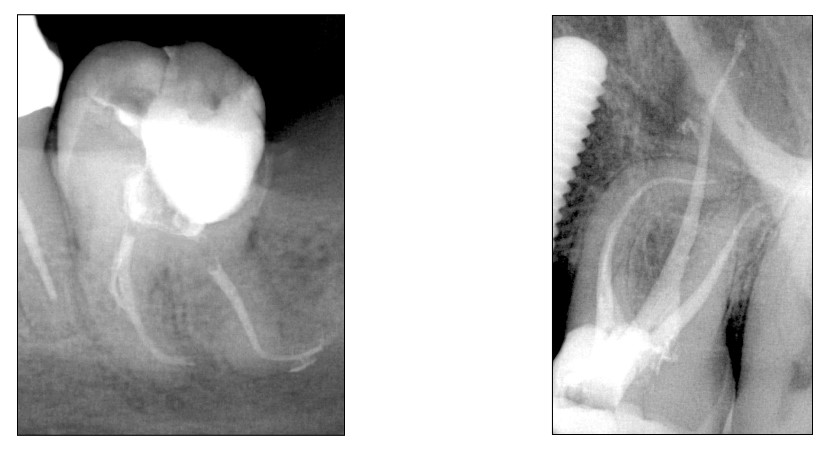

Foto molare

*Molare inferiore con curvature severe, gestito in sicurezza con Hyflex EDM

*Molare superiore con curvature severe, gestito in sicurezza con Hyflex EDM